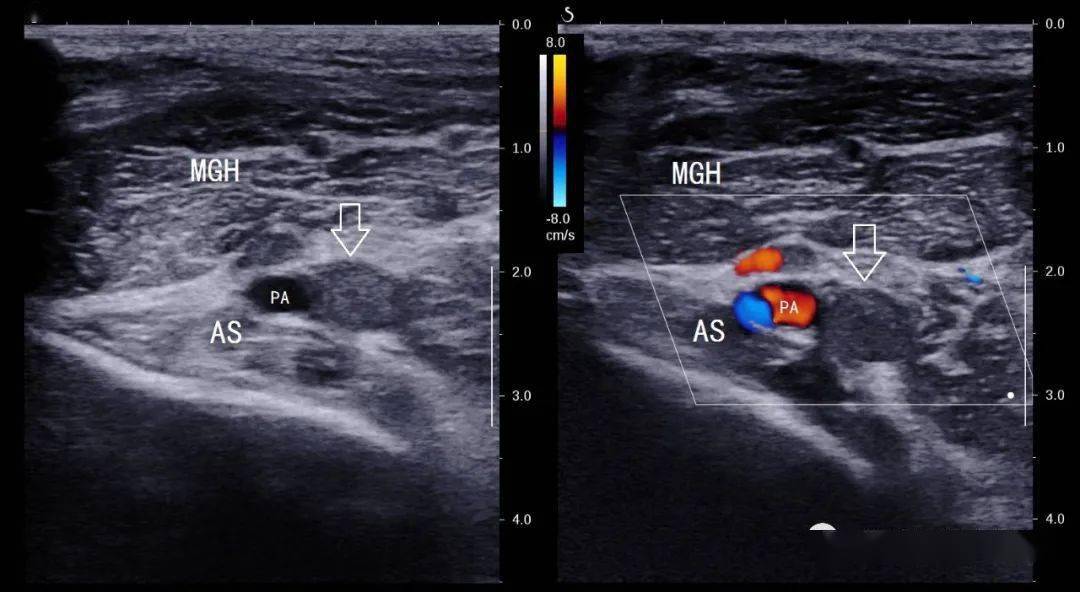

图文解码腘动脉陷迫综合征paes

图片尺寸900x1234